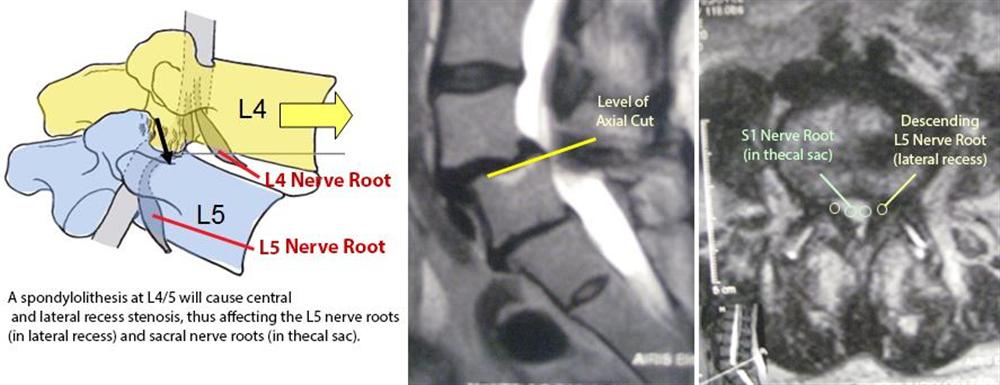

협부형은 위로 lysis가 위로 올라가기에 L4 증상이 나타남. - ⅲ. 퇴행성: 주로 40대 이후, M<F, 제4-5요추 호발, 후관절의 퇴행성 변화, 반복적인 굴곡-회전력

L5 증상이 나타남 - ⅳ. 외상성: 대부분 보조기 착용 치유가능

Spondylolysis는 어긋나면서 central canal은 오히려 넓어지고 exit foramen은 좁아져서 upper root증상

Degenerative는 그냥 spinal stenosis처럼 lateral recess 좁아져서 lower root 증상